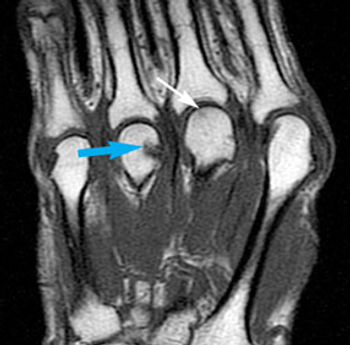

Ultrasound diagnosis of tenosynovitis has now been shown to be superior to clinical signs and symptoms (eg, early morning stiffness, symmetrical arthritis, and hand joint arthritis) in predicting early rheumatoid arthritis.

Evaluating a 29-year-old female business executive with complaints of joint pains and stiffness affecting both hands and wrists, both feet and her left knee. She has reported these symptoms for the past 3 weeks.